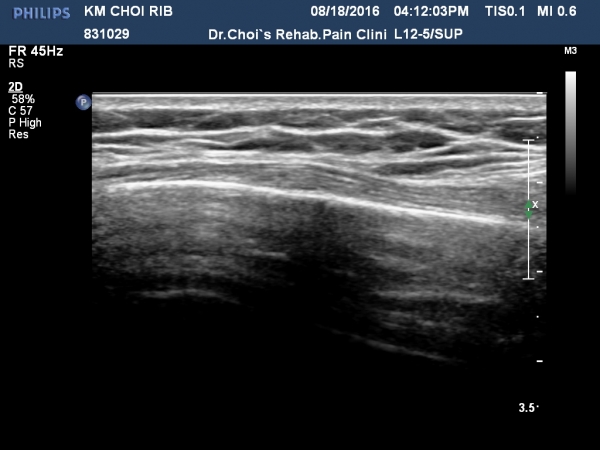

ÃÊÁø ½Ã °¥ºñ»À ÃÊÀ½ÆÄ°Ë»ç¿¡¼­ ÇÇÁú°ñ ¤·³à¼Ó¼º ¼Ò½ÇÀº º¸ÁöÁö ¾ÊÀ¸³ª

±æºñ»À Ç¥Ãþ¿¡ ±¹¼ÒÀûÀÎ ¿¬ºÎÁ¶Á÷ ºÎÁ¾ÀÌ °üÂûµÈ´Ù(»çÁø 1, 2, 3, 4).